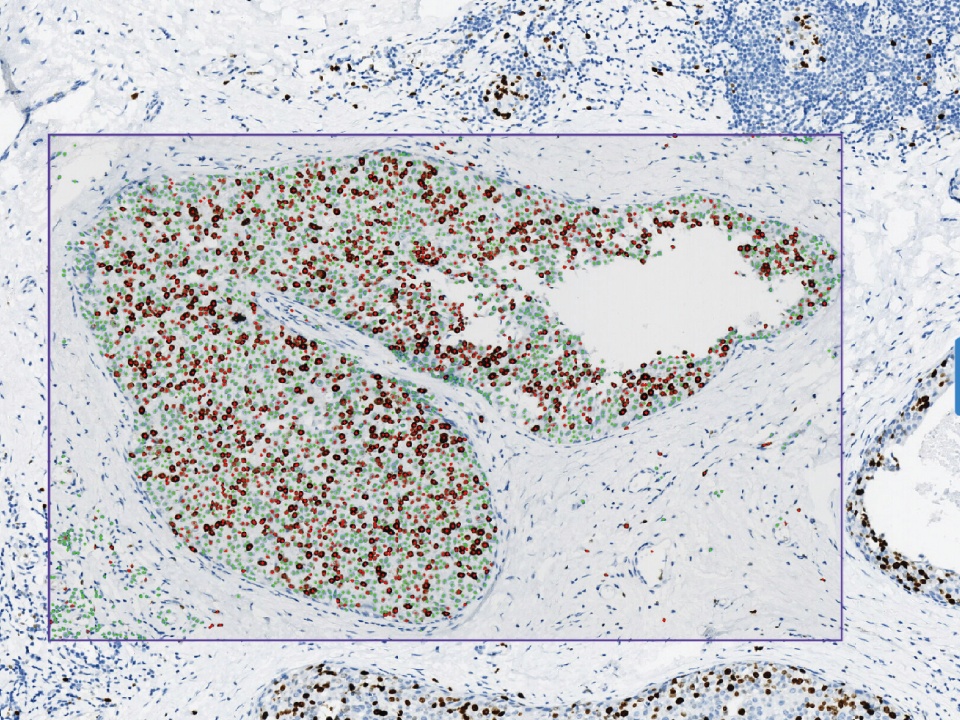

Immunohistochemistry Assistant Analysis Module

Whole slide analysis,intelligent cell counting. Algorithm intelligently segments the effective area to fit different diagnostic scenarios. Multiple staining images displayed on one screen for comprehensive comparative analysis. High concordance with the pathologist's interpretation with an accuracy of >0.94.

Immunohistochemistry Assistant Analysis Module

Whole slide analysis,intelligent cell counting.

Algorithm intelligently segments the effective area to fit different diagnostic scenarios.

Multiple staining images displayed on one screen for comprehensive comparative analysis.

High concordance with the pathologist’s interpretation with an accuracy of >0.94.